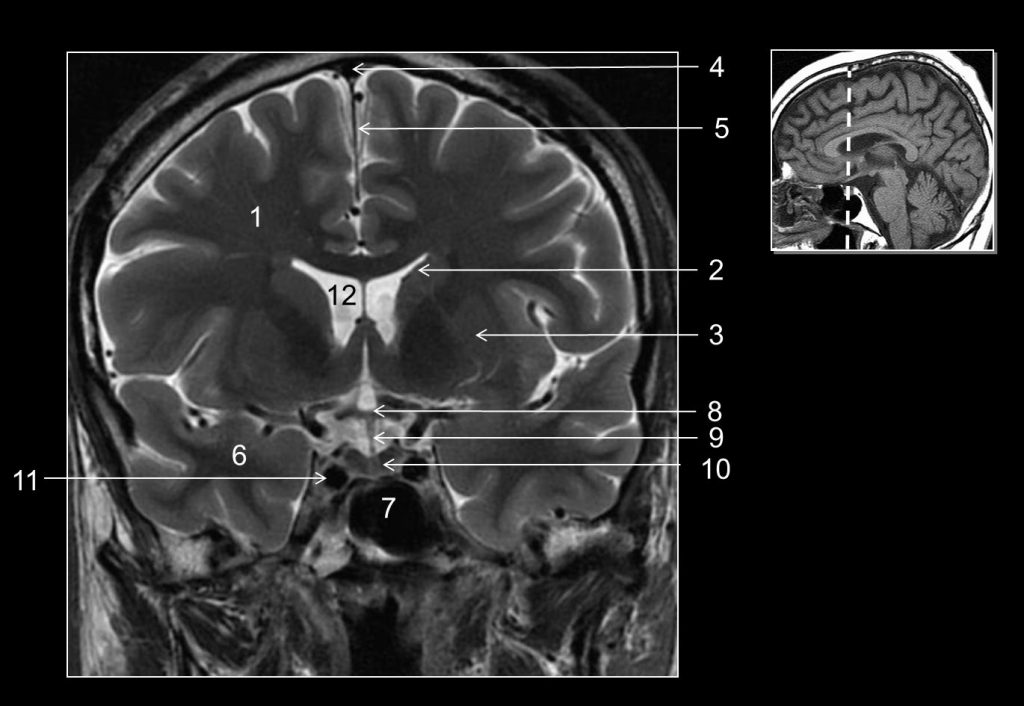

Fig. 48.10 Coupe frontale (IRM, ici en pondération T2).

1. Substance blanche du lobe frontal. 2. Noyau caudé. 3. Putamen. 4. Sinus sagittal supérieur. 5. Faux du cerveau. 6. Substance blanche du lobe temporal. 7. Sinus sphénoïdal. 8. Chiasma optique. 9. Infundibulum hypophysaire. 10. Antéhypophyse. 11. Artère carotide interne (dans la loge caverneuse). 12. Ventricule latéral.

Source : CERF, CNEBMN, 2022